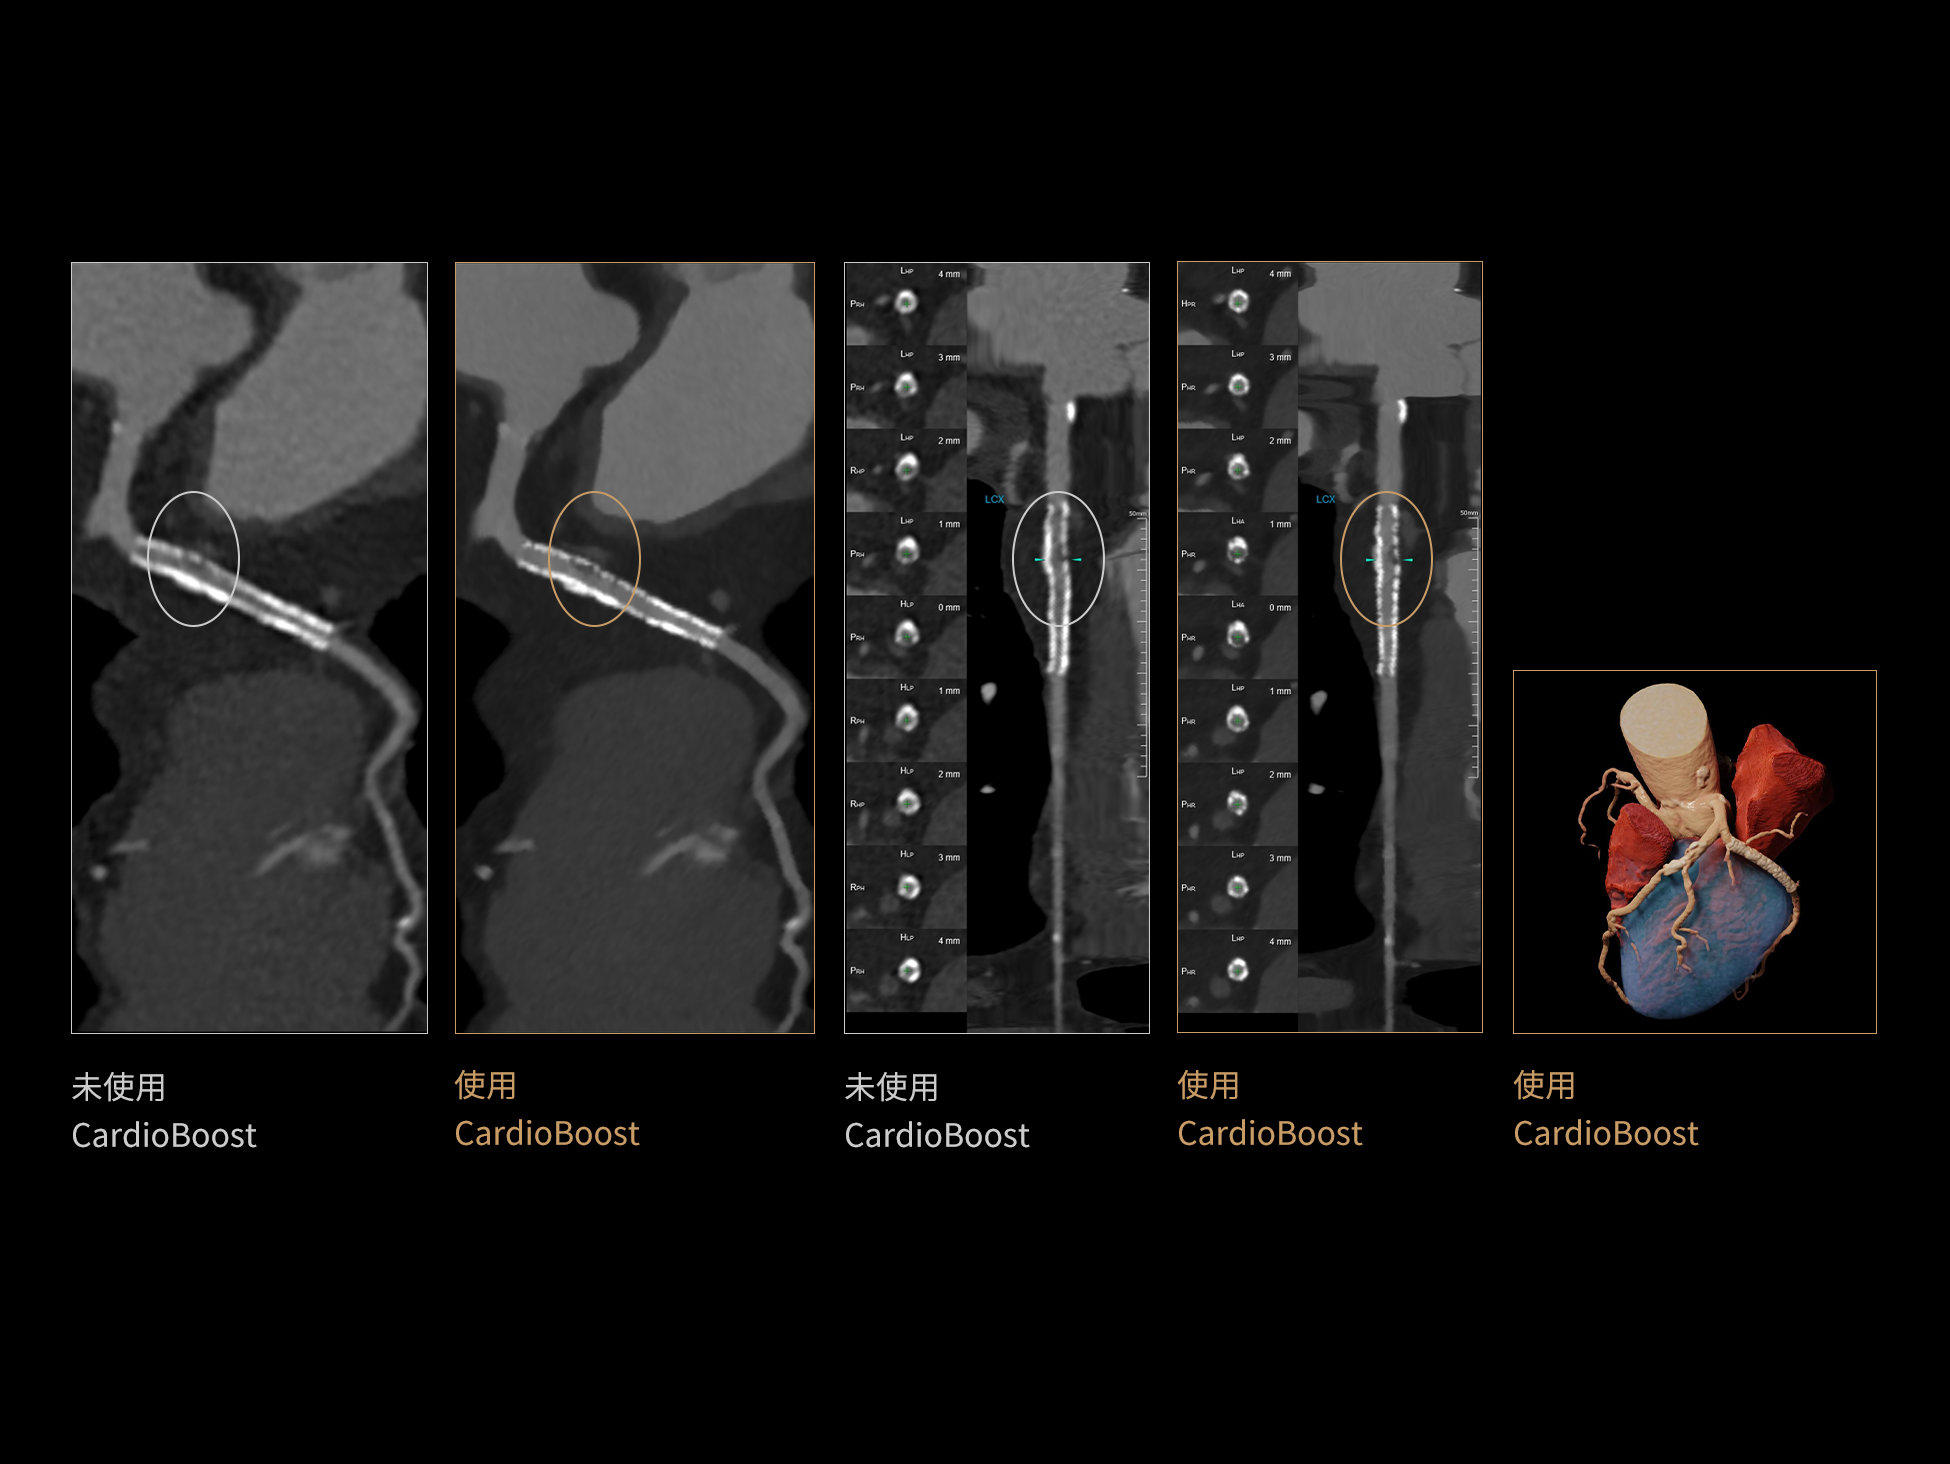

CardioCapture:AI冠脉运动追焦技术

CardioCapture 算法在冠脉运动伪影校正中采用全局化、系统化的处理策略。以目标时相为核心,重建多个相邻时相图像,利用深度学习技术提取连续时相中的冠脉树结构,构建时相间的运动模型,并对分段重建图像进行精准校正。通过这一过程,CardioCapture 可实现等效21 ms的超高时间分辨率,大幅提升冠脉图像清晰度与判读可靠性。

传统的血管提取通常基于CT值阈值和固定的冠状动脉模型,这种方法常常会失效,尤其是对于存在运动伪影的血管。 CardioCapture 算法基于深度学习网络,充分学习各类冠脉图像,以适应不同冠脉场景,精准高效完成冠脉及中心线提取,相较于仅基于CT 值和固定解剖模型的传统算法,CardioCapture 对于小血管及末端血管显示优势更加显著。

冠脉运动伪影校正过程

有效提取冠脉分支